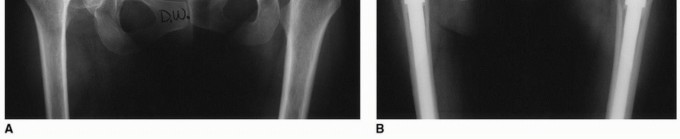

Radiographic Evaluation and Templating

Plain radiographs must include an anteroposterior (AP) projection of the pelvis, an AP of the involved hip, and a Lauenstein (frog-leg) lateral x-ray. Radiographic magnification markers (typically a 25 mm or 30 mm sphere) taped to the involved hip at the level of the greater trochanter allow for an accurate estimate of x-ray magnification. This permits precise digital templating of the femoral canal.

Templating a modular stem is a sequential process:

1. Distal Fixation: The distal stem is templated first to ensure adequate cortical contact (typically 4-6 cm of scratch fit in the diaphysis) while bypassing any stress risers or deformity apices by at least two cortical diameters.

2. Proximal Fill: The proximal body is then templated to fill the metaphysis and reconstitute the medial calcar.

3. Offset and Length: The modular neck or proximal body geometry is selected to recreate the center of rotation, horizontal offset, and leg length.

Computer tomography (CT) scans are rarely indicated for routine THA but are invaluable in complex cases to provide a highly accurate assessment of native femoral anteversion, precise femoral canal dimensions, and acetabular bone stock. Scanograms or full-length standing AP radiographs of the lower extremities may be useful to more accurately assess true limb length inequalities and global coronal alignment.